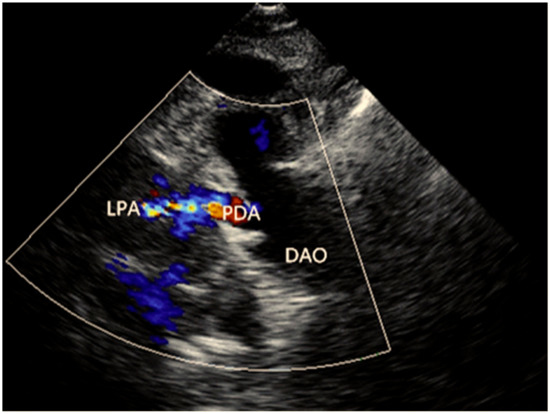

- Abhinav, P.; Zhang, G.F.; Zhao, C.M.; Xu, Y.J.; Wang, J.; Yang, Y.Q. A novel KLF13 mutation underlying congenital patent ductus arteriosus and ventricular septal defect, as well as bicuspid aortic valve. Exp. Ther. Med. 2022, 23, 311. [Google Scholar] [CrossRef]

- Ke, Z.P.; Zhang, G.F.; Guo, Y.H.; Sun, Y.M.; Wang, J.; Li, N.; Qiu, X.B.; Xu, Y.J.; Yang, Y.Q. A novel PRRX1 loss-of-function variation contributing to familial atrial fibrillation and congenital patent ductus arteriosus. Genet. Mol. Biol. 2022, 45, e20210378. [Google Scholar] [CrossRef]

| II-1 | Male | 62 | PDA, PS | +/− |

| II-3 | Male | 60 | PDA | +/− |

| II-8 | Female | 55 | PDA | +/− |

| III-3 | Male | 37 | PDA, PS | +/− |

| III-8 | Female | 34 | PDA | +/− |

| III-13 | Male | 31 | PDA | +/− |

| IV-2 | Female | 13 | PDA, PS | +/− |

| IV-8 | Male | 5 | PDA | +/− |